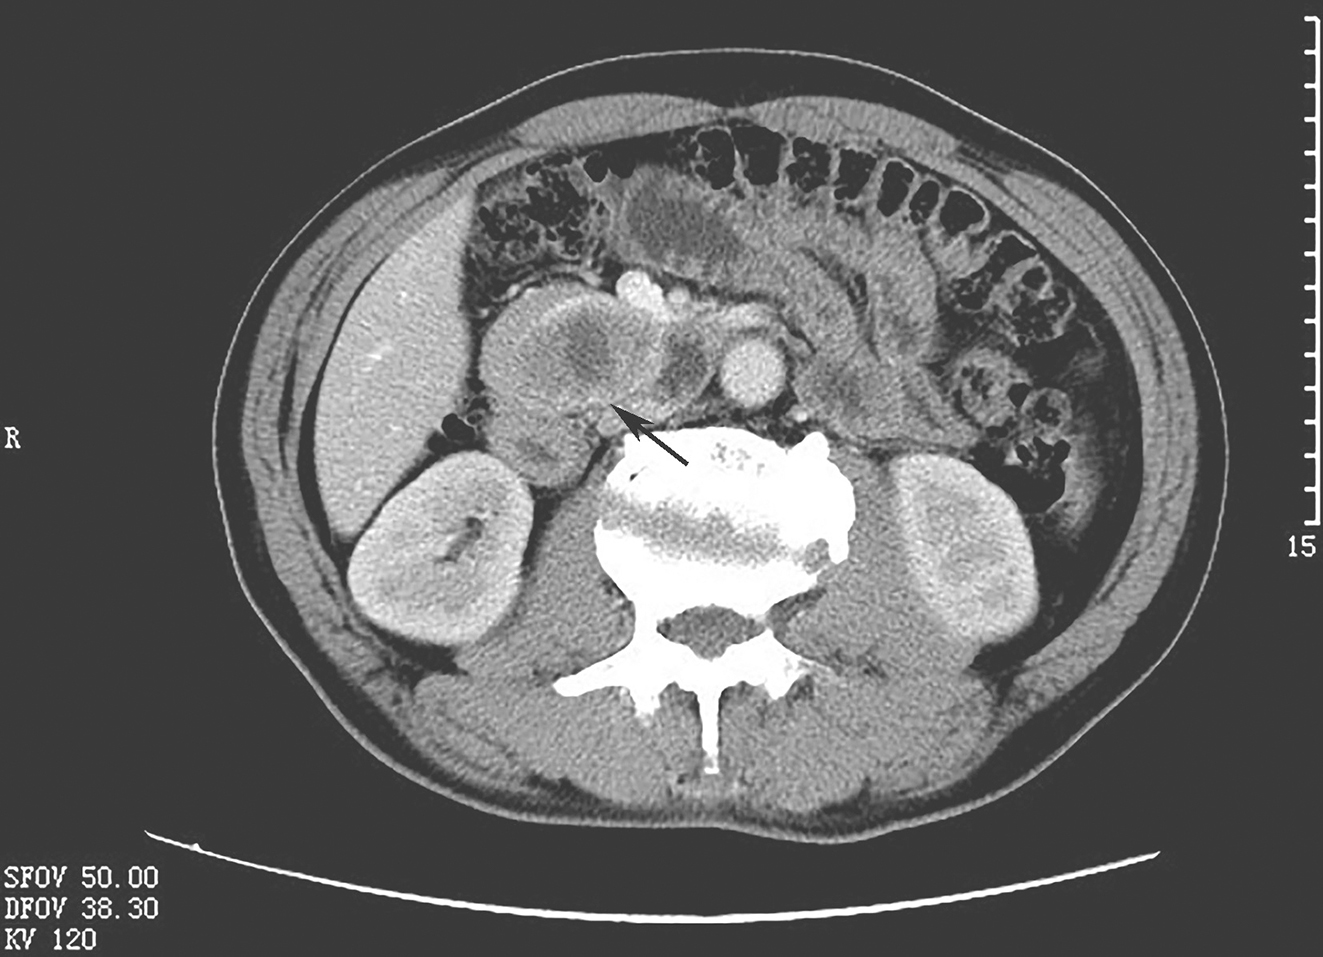

一例病情复杂的胃肠间质瘤的诊治经验分享

1小时条评论外科手术是可切除胃肠间质瘤(gastrointestinalnbsp;stromalnbsp;tumor,GIST)的首选治疗方法,但对于中高危患者而言,单纯手术往往难以实现长期生存。随着c-KIT/PDGFRAnbsp;基因功能性突变的发现,胃肠间质瘤的...